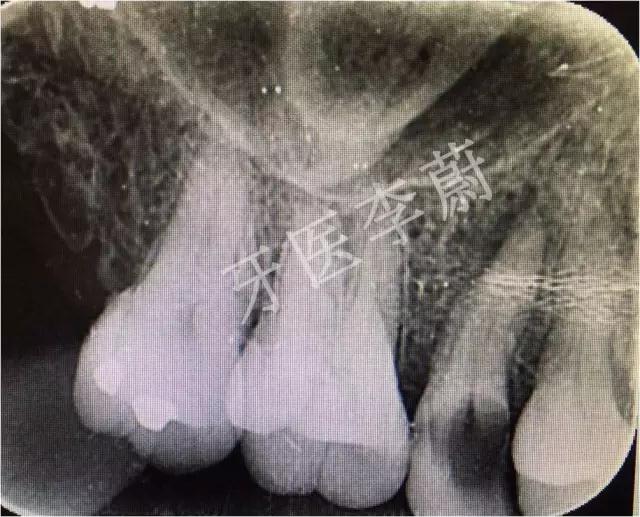

X片示:15残冠影,根尖有骨密度降低影。

曲面断层片